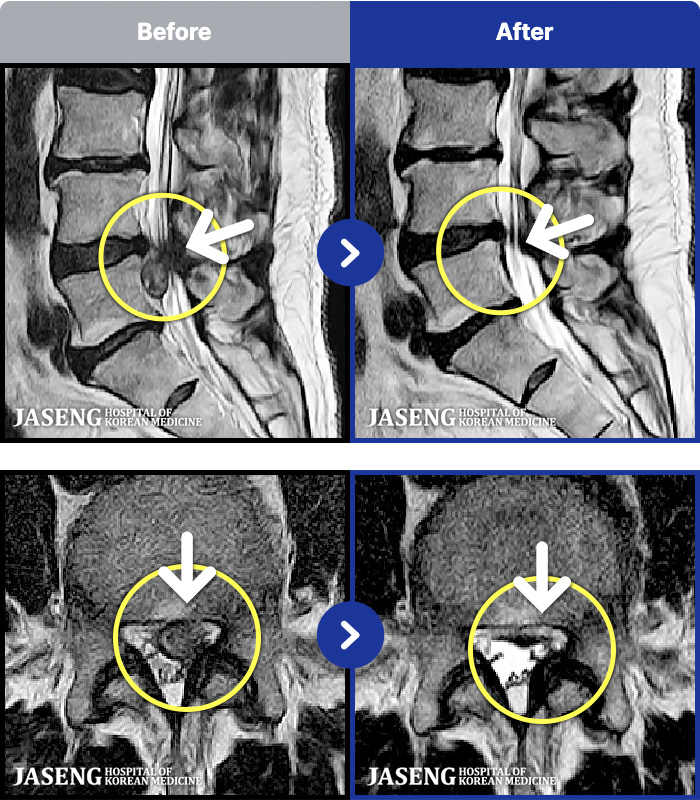

MRI ġ

MRI ũ ʸ Ȯϼ.

㸮 ؼ ̱ ư ϴ.